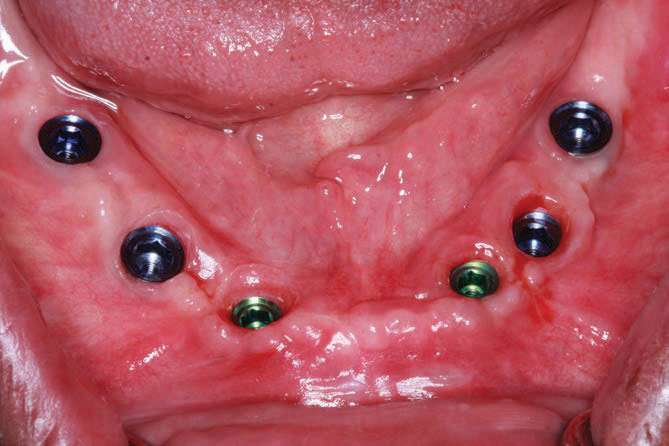

BioHorizons implants were selected in order to increase bone-implant contact, as the threads are designed to optimize bone contact as well as utilize Laser-Lok technology (BioHorizons) to hold the hemidesmosomes of the tissue so that the tissues would be less friable and provide for better tissue dynamics. Upon implant placement, a Piezo surgical device (PIEZOSURGERY by Mectron) was used to remove sharp lips of bone as the implants were countersunk by design. The PIEZOSURGERY by Mectron works by using micro-vibrations to cut bone while minimizing soft-tissue trauma. The device and its internal irrigation provides an almost blood-free foundation while cleaning around the implants and removing unwanted tissues. The cutting is micrometric, and the micro-vibrations not only cut bone but help collect bone particles to be used in the defects around the implants so the autogenous shavings can be placed adjacent to the exposed threads or fenestrations[14] (Figure 7).

The BioHorizons implants were placed with a good A-P spread, and the bone in the anterior mandible was left in case it was needed at the uncovery appointment (Figure 8). At the uncovery visit, the LightScalpel laser was used to perform a trephine of the posterior implants by placing the surgical guide, marking the osteotomy sites with a Dr. Thompson’s marking stick, and (using a super-pulsed 2W setting) to gently remove the cuff of tissue over the implants (Figure 9). In the anterior mandible, a full-thickness flap was done, and the remaining bone was removed with the PIEZOSURGERY device (Figure 10). The peri-mucosal healing abutments were placed, and a soft-tissue conditioner was placed in the lower denture (Figure 11). After one month of healing, the patient was ready for impressions (Figure 12).